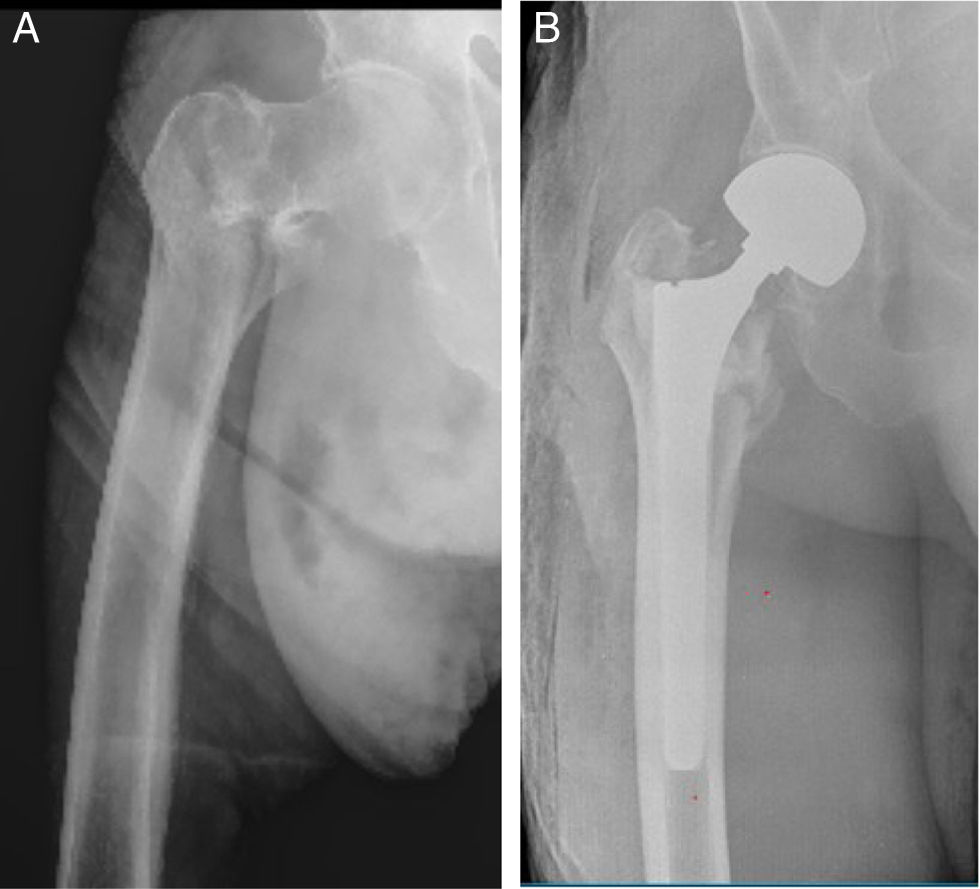

A non-cemented, tapered, grooved femoral stem was used for distal fixation, selected according to the patient's anatomical characteristics and bone quality. The stem used in this study, MD6® (Vincula, Rio Claro, Brazil), is made of titanium alloy and has a highly textured surface along its entire length. The stem features eight longitudinal grooves with relatively sharp edges designed to achieve effective anchorage with the femoral cortex (Fig. 1). The average stem length was 180mm, and in all cases, a 28mm femoral head was used along with a bipolar acetabular component. The femoral canal was always reamed manually.

Component alignment was adequate in all cases (Fig. 2). Diaphyseal osseointegration was evident on follow-up radiographs at 6 months post-surgery. The radiographic criteria of Engh et al.7 were followed for evaluating the fixation of uncemented femoral stems, assessing the absence of peri-implant radiolucent lines in Gruen zones 2, 3, 4, 5, and 6, signs of bone remodelling around the stem, and confirming implant stability one year after the procedure. No subsidence greater than 5mm was observed, and no femoral pain was reported in any of the patients.